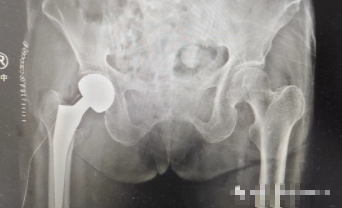

通过充分的术前准备,手术团队为张奶奶进行了右侧人工股骨头置换术,手术仅用时45分钟便顺利完成,患者各方面指标均达到预期标准。术后第二天,张奶奶已在医生指导下进行下床活动,开始进入康复期。

术后